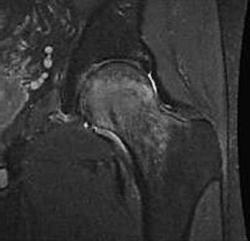

Пример transitional osteoporosis of the hip:

МРТ сустава выявило выраженных отёк в шейке и головке бедренной кости:

Слева отмечается повышение сигнала от костного мозга; справа костный мозг гипоинтенсивен (норма при использовании посследовательней с подавлением сигнала от жира)